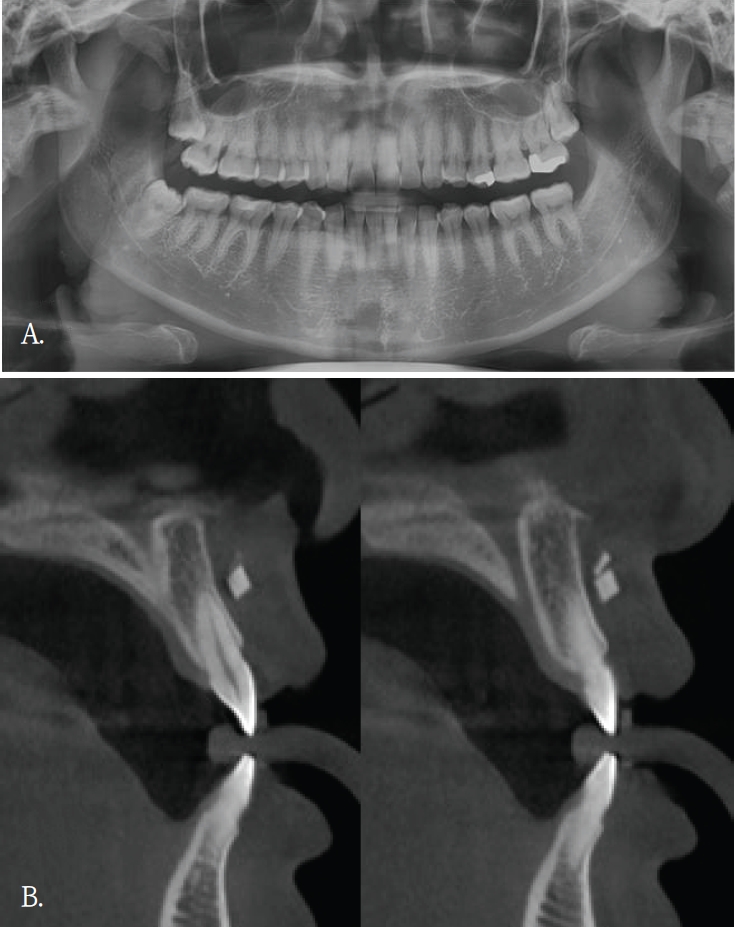

좌측 안면 부종으로 타원에서 의뢰된 30대 여자환자의 파노라마방사선영상에서 좌측 하악체 및 하연부를 따라 길이가 약 7cm로 측정된, 가는 선 모양의 방사선불투과성 이물질이 관찰되었다(Fig. 3A). 그러나 파노라마방사선영상에서 이물질의 협·설측 위치 및 하악골 내 포함여부를 명확히 판단하기 어려웠다. 이에 위치 및 주변 구조물과의 관계를 평가하기 위해 콘빔CT검사를 시행하였다. 콘빔CT에서 이물질은 좌측 하악체 외측 피질골 바깥의 협측 연조직에서 관찰되었다(Fig. 3B). 영상소견을 바탕으로 구강 내 접근을 통해 외과적 제거술이 시행 되었고 제거된 이물질은 부러진 주사바늘로 확인되었다.

A. Panoramic radiograph shows a long, thin, linear radiopaque foreign body along the left mandibular body and inferior border (arrow). B. Coronal cone-beam computed tomographic image demonstrates that the linear radiopaque foreign body is located in the buccal soft tissue lateral to the mandible (arrow).

증례 5와 같이 파노라마방사선영상에서 모호하게 관찰되었거나 증례 3과 4같이 파노라마방사선영상에서 협-설위치를 명확하게 알 수 없었던 경우, 콘빔CT영상에서 임상적으로 의미있는 이물질임을 확인되었고 외과적 치료가 시행되었던 증례들이다. 특히, 이들 소견은 악골이 아닌 안면 연조직 부위에서 관찰되어, 주의 깊은 영상판독의 중요성을 다시금 일깨워 준다.